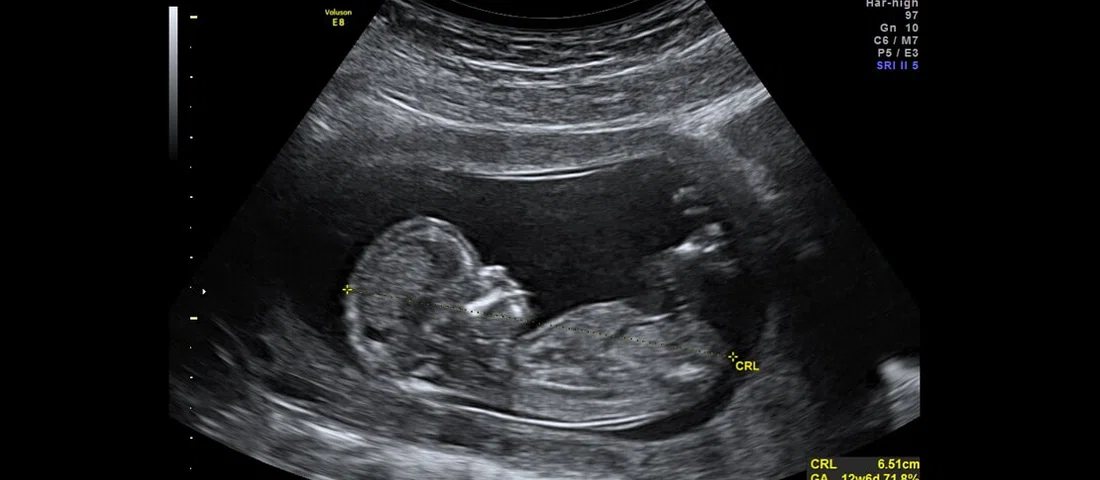

اودد وانونو، سرپرست تحقیقات شرکت چکپوینت در زمینه آسیبپذیریها، با یک بیمارستان در تلآویو روی سیستم اولتراسوند کار میکند که ممکن است در آینده نزدیک در سراسر بیمارستانهای دنیا بهکار گرفته شود. او در مصاحبهای با رسانهها در کنفرانس RSA 2019 گفته است که طی آزمایشهایشان روی این سیستم، متوجه شدهاند که تنها با دو کلیک میتوان روی این سیستم تغییرات ایجاد کرد. از آنجایی که شبکه بیمارستانها و دستگاههای هوشمند متصل به این شبکهها، بهراحتی قابل شناسایی و در دسترس هستند، این مساله به راحتی، قابل انجام است.

در همین رابطه وانونو گفته است که نیازی به مهندسی معکوس سیستم اولتراسوند و استفاده از مهارتهای خاص برای هک دستگاه وجود نداشته و تنها بهواسطه استفاده از ویندوز ۲۰۰۰ روی این سیستم، عملیات هک با موفقیت انجام شده است. سیستم عاملی که به پایان عمر خود رسیده و دیگر توسط مایکروسافت بهروز نمیشود. به همین دلیل، تیم تحقیقاتی چکپوینت بهسادگی توانسته است با استفاده از یک آسیبپذیری قدیمی و شناخته شده در این سیستم، به هک آن دست بزند.

در همین رابطه وانونو گفت است که ما سه حمله مختلف را انجام دادیم که همه آنها بسیار ساده بودند. اول، توانستیم تمام اسکن بیماران را در یک چشم بر هم زدن به دست آوریم. سپس، اسامی بیماران را جابهجا کرده و در نهایت باجافزاری را روی آن دانلود کردیم.